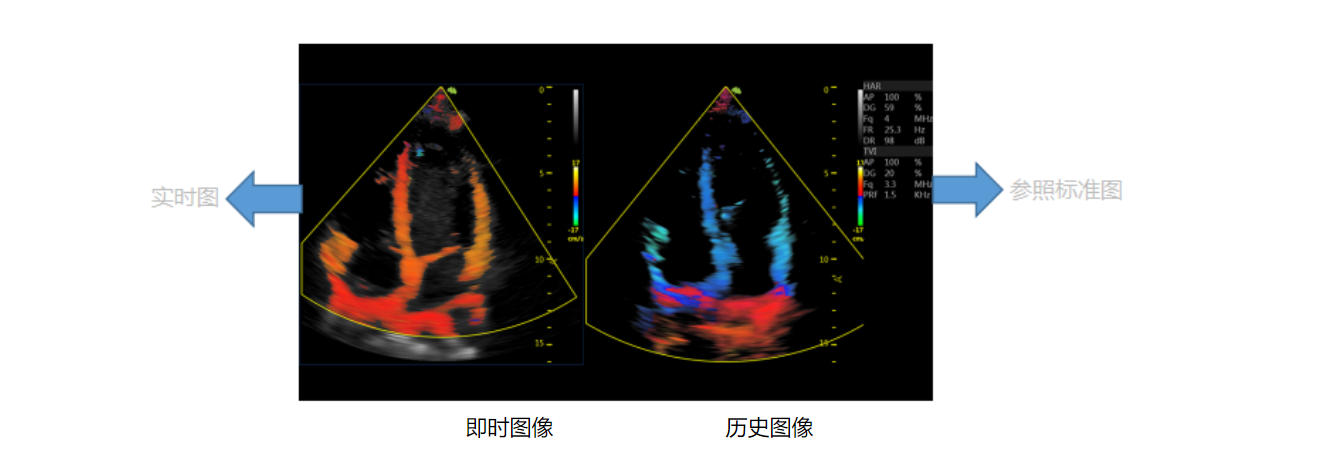

Easy Compare 跟踪对比

大鼠胎鼠心脏血流 大鼠心尖四腔